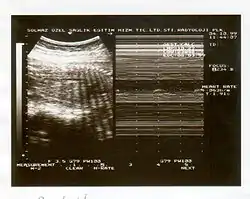

El perfil biofísico fetal es un método ecográfico basado en un sistema de puntuación, utilizado en medicina para determinar el bienestar de un feto durante un embarazo de alto riesgo.[1] Por lo general se indica cuando el test de reactividad fetal arroja resultados no reactivos, aunque un obstetra puede solicitar la valoración por otras causas.

El perfil biofísico es una combinación de marcadores agudos y crónicos. La reactividad cardíaca fetal, los movimientos corporales fetales, los movimientos respiratorios y el tono fetal se describen como marcadores agudos, mientras que el volumen de líquido amniótico, junto con las características de la placenta se han considerado como marcadores crónicos.[2] El objetivo del perfil biofísico fetal es de identificar oportunamente aquellos fetos con hipoxia y acidosis, con el fin de tomar la conducta perinatal más adecuada, evitando la muerte intrauterina y la morbilidad perinatal.[3]

- Determinación de la actividad o reactividad cardíaca fetal, también conocida como una prueba de reactividad fetal, en el que la aceleración de la frecuencia cardíaca fetal se comparan, en el tiempo, con los movimientos fetales a ver si correlacionan. --> Este criterio se ve en el trazado de monitoría fetal. (2 aceleraciones en 20 minutos)